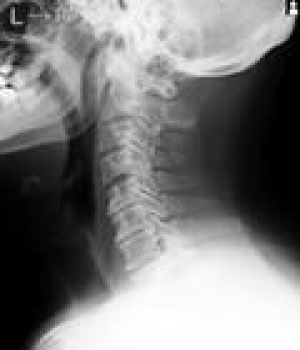

MRIはMagneticResonanceImageの略で強い磁石と電波によって人体の構造を見ることが出来る検査です。

頭部領域から脊椎・関節・骨疾患、腹部に至るまで全身部位の診断に役立ちます。

脳梗塞、脳腫瘍、脳動脈瘤、頚髄症、椎間板ヘルニア、脊柱管狭窄症、脊椎圧迫骨折、腱板損傷、各関節靭帯損傷、半月板損傷、骨壊死、肉離れ、骨腫瘍、軟部腫瘍、炎症、など